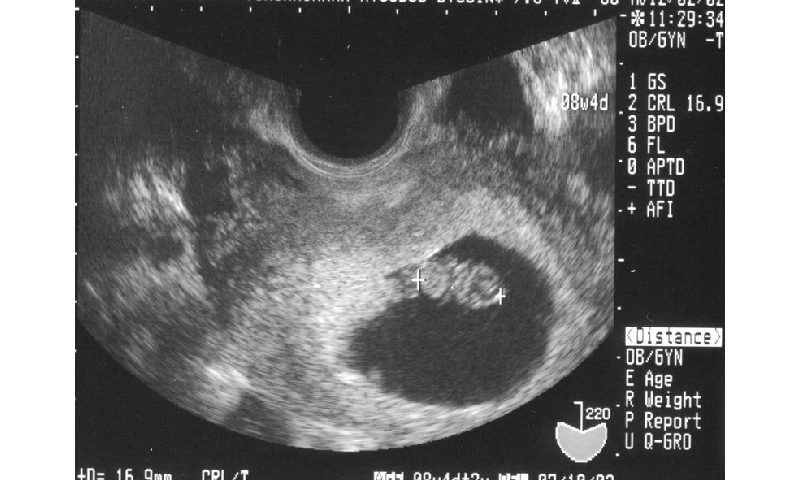

Hình ảnh siêu âm thai nhi 6 tuần tuổi cho thấy cơ thể em bé mới chỉ có thể nhìn thấy chiếc đầu và trán rất to, thân mình bé xíu, đường nét khuôn mặt ngày càng rõ nét. Đặc biệt, bé bắt đầu hình thành chóp mũi, đôi mắt bắt đầu tách ra dần về phía thái dương hơn, lỗ mũi cũng đã dần xuất hiện. Bàn chân và bàn tay của bé từ từ nhô ra giống như cái mái chèo. Trong tuần thứ 6, các van tim của bé đã được hình thành, đường dẫn không khí từ cổ họng đến phổi cũng đã xuất hiện. Ngoài ra, bán cầu não cũng đang phát triển mạnh mẽ, các cơ quan khác như gan, tủy xương, tuyến tụy, ruột thừa cũng lần lượt xuất hiện. Một đoạn ruột của thai nhi sẽ hình thành dây rốn để lấy dưỡng chất, oxy từ mẹ và đẩy chất thải ra khỏi cơ thể bé.